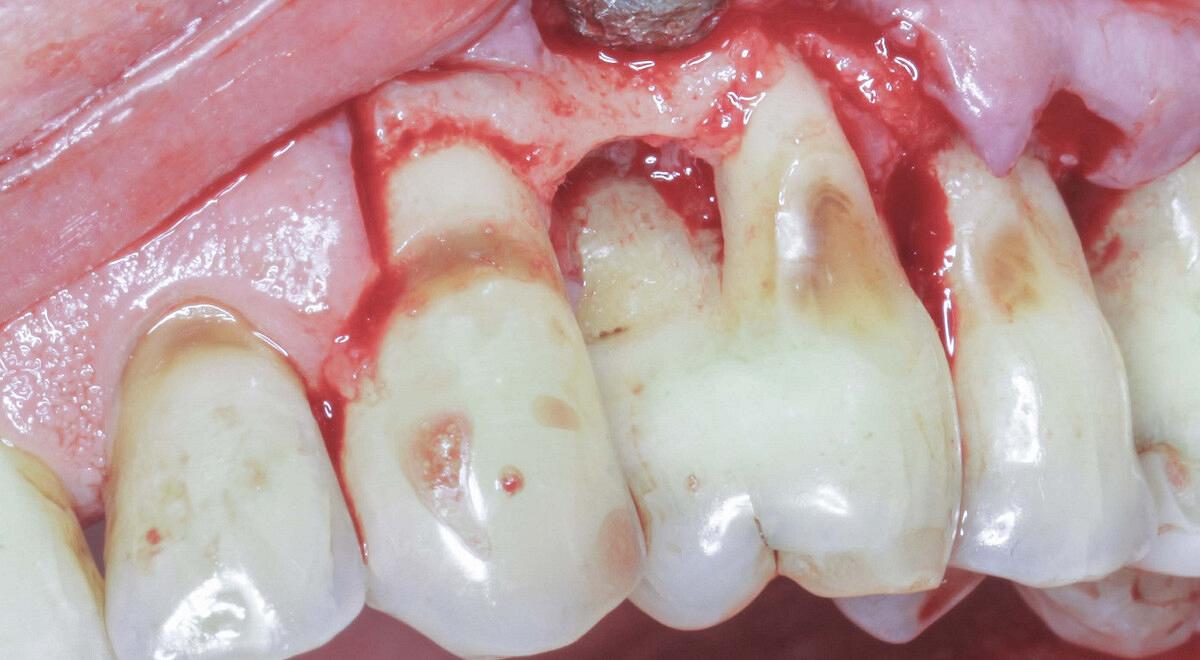

Chirurgie kan na een initiële parodontale behandeling noodzakelijk zijn om verdere pocketdieptereductie te realiseren. In deze nascholing leert u wanneer een chirurgische benadering zinvol is en welke patiëntgebonden en lokale factoren bepalend zijn voor het behandelresultaat. Denk aan mondhygiëne, rookgedrag, medicatiegebruik, maar ook aan anatomische kenmerken op gebitselementniveau. De nascholing behandelt twee hoofdbenaderingen: resectief en regeneratief. U krijgt inzicht in de verschillen tussen beide strategieën en leert welke technieken en materialen daarbij toegepast worden. Ook wordt er aandacht besteed aan flapsluiting, waarbij de positionering afhankelijk is van de gekozen chirurgische benadering. Verder komt postoperatieve zorg aan bod, waaronder wondverzorging, pijnbestrijding en nazorginstructies voor de patiënt. U leert hoe u complicaties herkent en wat u kunt doen bij veelvoorkomende problemen zoals nabloeding, perforatie of botsekwesters. Deze nascholing biedt praktische handvatten om chirurgische parodontale behandelingen goed te indiceren, voor te bereiden, uit te voeren en op te volgen.